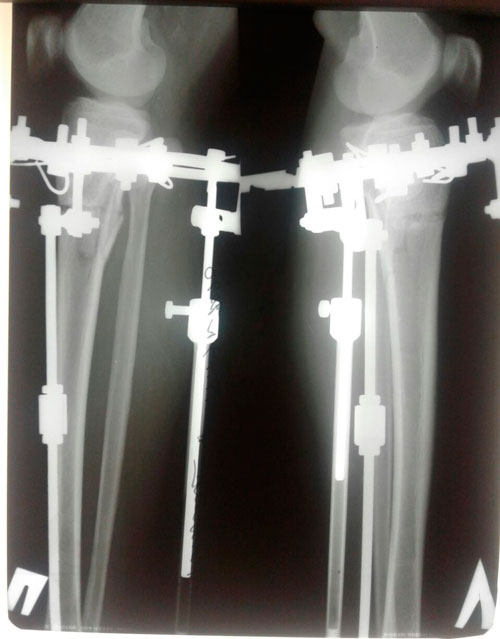

Исходник 28 лет Актобе.

Дата операции 14.02.2018г.

Дата снятия аппаратов 12.06.2018г.

Срок лечения 120 дней.

Данная пациентка сняла аппараты (без разрешения Клиники) у себя в городе.

По условиям договора: Пациент обязан снимать аппараты в Клинике! В противном случае, Клиника не несёт ответственность за последствия и результат.